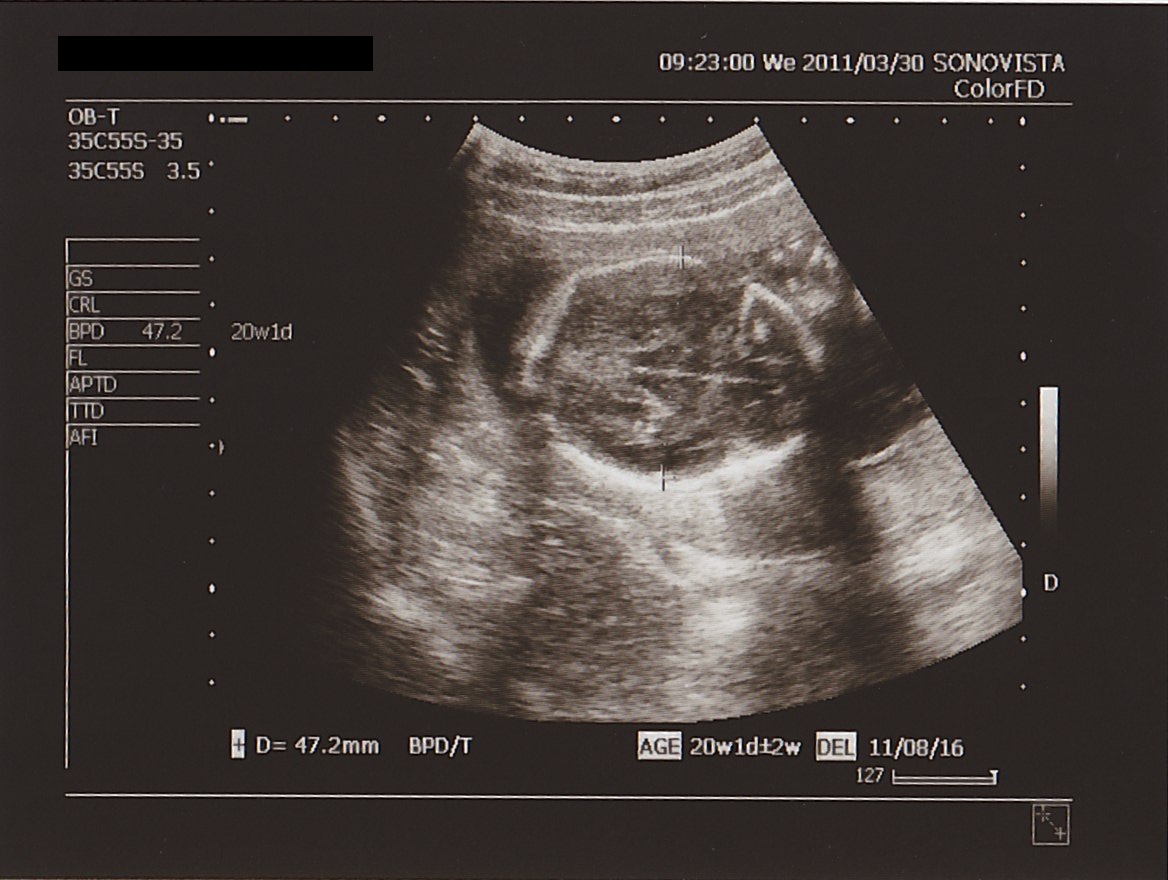

さて エコー。

まずは あたま。

前回の サイズ ( 横幅 ) は 35ミリ。

4週間後の 今日は…

▲ 横幅 47.2ミリ。

想定週数とも ほとんど 合致。

順調に おおきくなっている みたいです。